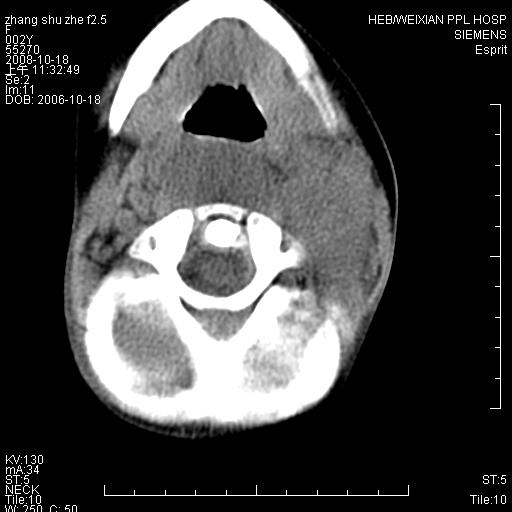

以下是引用dyqct在2009-2-10 21:04:00的发言:[br]年龄?性别?有发烧吗?[br]鼻咽部、口咽部、喉咽部及颈椎前间隙广泛肿厚,明显占位效应并致相应组织变形。ct值22-28hu。[br]考虑:1、颈前脓肿可能性大;[br] 2、建议增强或治疗后复查。

以下是引用jiangjing在2009-2-11 11:37:00的发言:[br]急性病程,鼻咽部、口咽部、喉咽部及颈椎前间隙广泛肿厚,明显占位效应并致相应组织变形.考虑颈部感染性病变(脓肿?);建议行进一步检查。